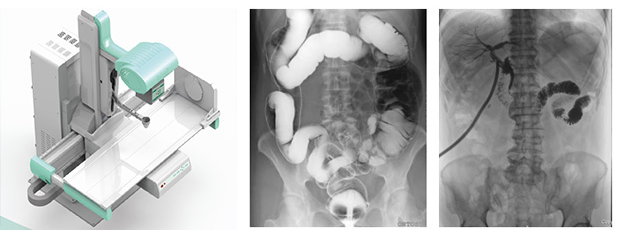

動(dòng)態(tài)DR可以理解為一種不同角度觀察器官運(yùn)動(dòng)的X光視頻。常規(guī)的靜態(tài)DR更多的顯示的是器官的投影像,單一角度單一時(shí)間點(diǎn)很難發(fā)現(xiàn)細(xì)微病灶。而真正的動(dòng)態(tài)DR可以從不同的角度、時(shí)間來觀察器官的運(yùn)動(dòng),診斷準(zhǔn)確率會(huì)大大提升。動(dòng)態(tài)DR的多角度檢查,其視覺效果上有點(diǎn)類似于CT

從功能上來說,真正的動(dòng)態(tài)DR是一款能夠數(shù)字拍片、數(shù)字透視、數(shù)字造影的多功能DR

從技術(shù)上來說,真正的動(dòng)態(tài)DR是使用多功能動(dòng)態(tài)數(shù)字化探測(cè)器成像的直接數(shù)字化X射線攝影系。

從臨床上來說,真正的動(dòng)態(tài)DR具有大幅面(17inch×17inch)高清拍片、大幅面(17inch×17inch)透視、視頻實(shí)時(shí)保存回放、可視化造影、毫秒級(jí)點(diǎn)片等基礎(chǔ)功能,以及斷層融合、數(shù)字減影等延展性功能。